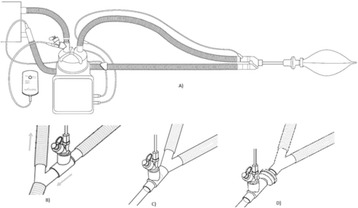

P226 - A device for emergency transtracheal lung ventilation

D. Pavlovic, L. Lewerentz, A. Spassov, R. Schneider